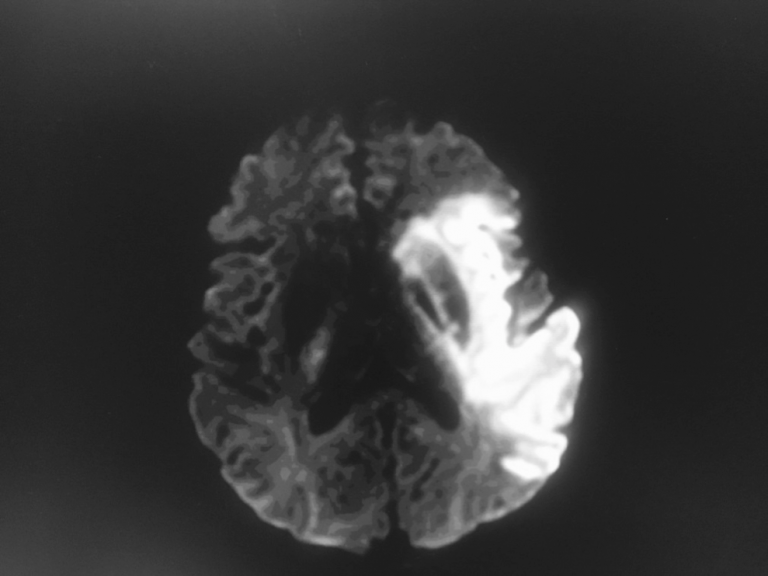

Meningite A Streptococcus Pneumoniae Et Vascularite Cerebrale Figure 1c

Meningite A Streptococcus Pneumoniae Et Vascularite Cerebrale Figure 1b

Meningite A Streptococcus Pneumoniae Et Vascularite Cerebrale Figure 1a